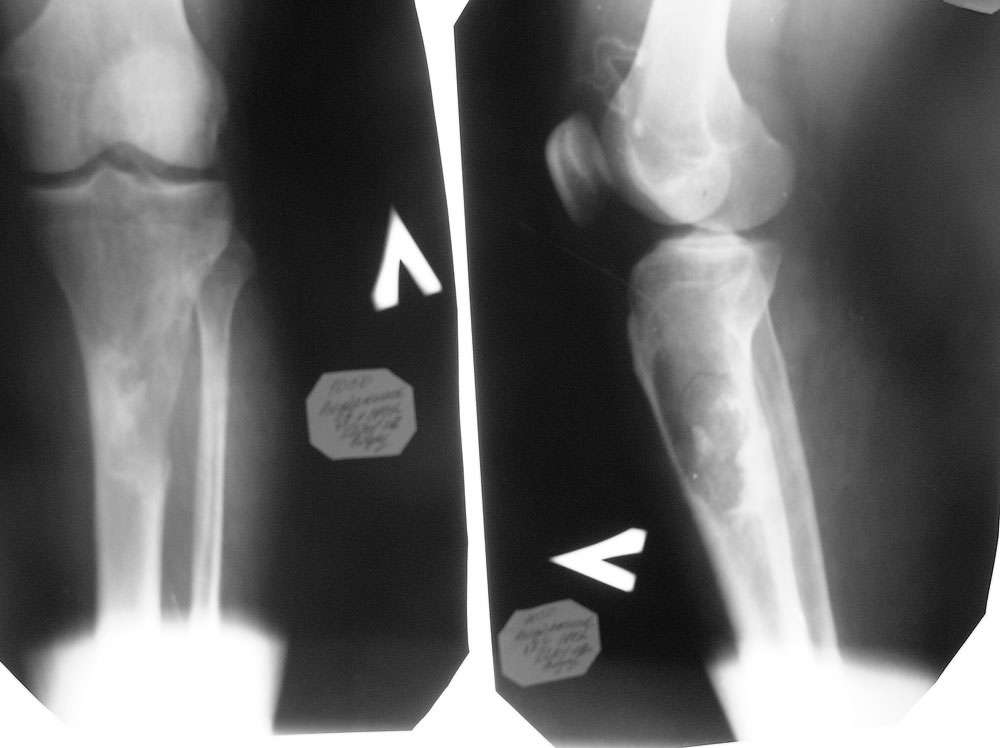

Пациент 31 года мужского пола, с патологическим незавершенным перелом верхней трети голени с очагом деструкции бльшого размера поступил к нам в клинику сегодня. Помогите определиться с тактикой лечения. Сроки биопсии, делать ли резекцию опухоли одновременно с биопсией и как замещать дефект. Поделитесь размышлениями, пожалуйста.

Судя по снимкам ,идет речь о остеолитическом повреждении кости состровами склерозной костной ткани ,Образование эксцентрично метафизо диафизарно сразрушением кортекса без четких границ,без выраженной периостальной реакции ,Ясно видно вовлечение прилежащих мягких тканей в процесс.

На рентгенограммах в области проксимального мета-диафиза б/берцовой кости больше латерально определяется значительных размеров остеолитическая деструкция с нарушением кортикального слоя и выходом "мягкотканного компонента" патологического образования за пределы кости. Медиальнее участка деструкции зона остеосклероза.